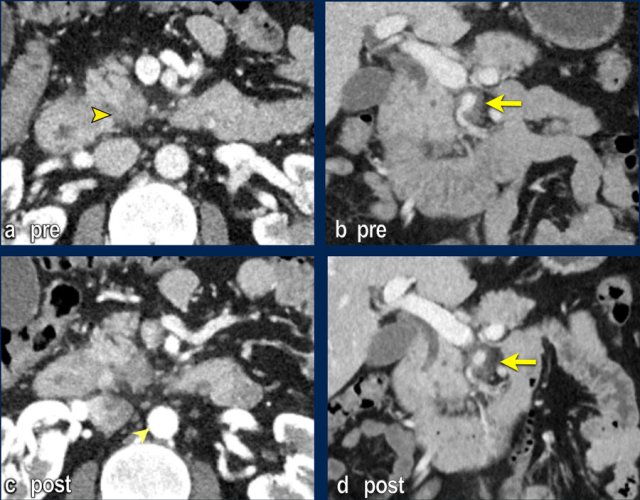

Images

The coronal reformat (a) shows a small tumor in the ampullary region (arrowhead), with obstruction of both the common bile duct (CBD) and pancreatic duct (PD). In absence of local invasion this is regarded as a resectable lesion.

The axial CT (b) however shows hypertrophy of the peripancreatic arcade (arrows), highly suggestive of a significant stenosis of the celiac trunk.

The celiac trunk stenosis is shown on sagittal MIP (arrow in c).

The collateral bloodflow to the hepatic artery via the pancreaticoduodenal arcade (stippled arrow) is nicely appreciated on a coronal MIP (d).

Axial CT (a) before neoadjuvant treatment shows a tumor on the medial side of the pancreatic head (arrowhead), irresectable based on extensive perineural growth with 360 degrees encasement of the SMA (arrow in b, coronal reformat).

Follow-up CT after 8 cycli of FOLFIRINOX (c,d) shows stable disease with persistent encasement of the SMA. The process was resectable on explorative laparotomy. T3bN2R0 on pathological exam.